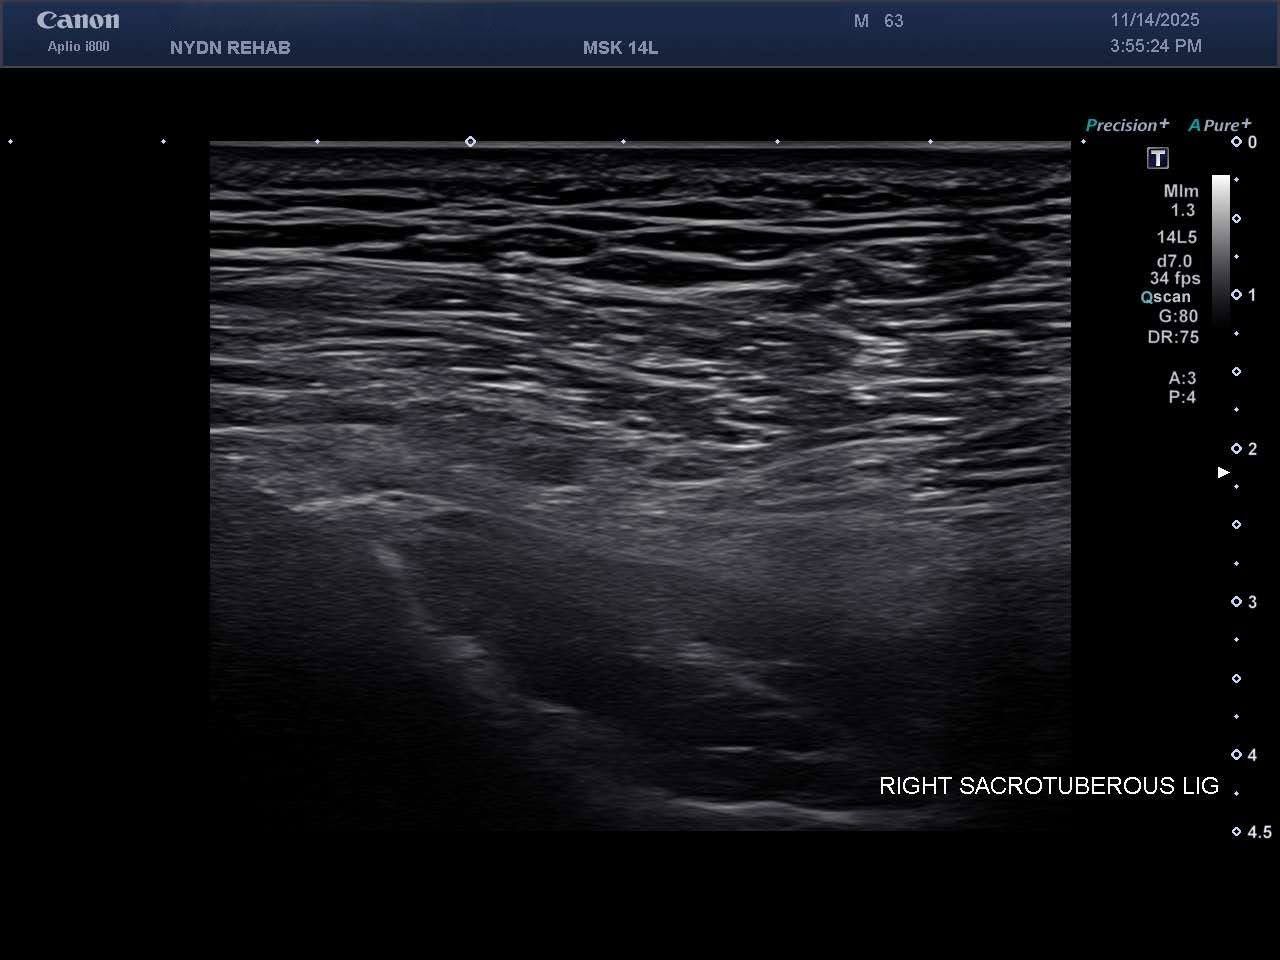

Ultrasound Images of SIJ Ligaments

• Sacrotuberous ligament thickening and enthesopathy